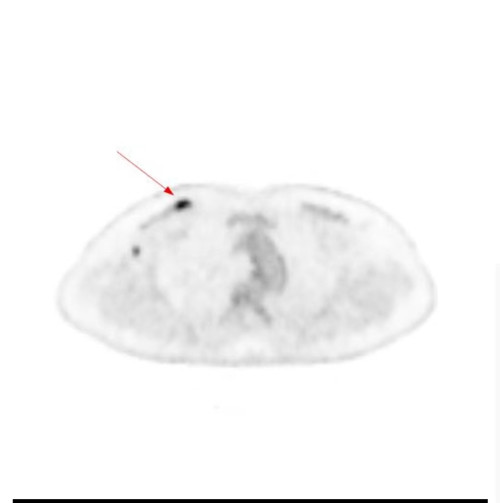

PETCT显示右侧乳腺内糖代谢明显增高的结节和腰椎的转移癌

问题来了,彭女士腰椎转移癌原发灶在哪里?是甲状腺癌吗?因关系后续治疗方案,在医生的建议下,彭女士到湖南省人民医院PET影像中心进行PET/CT扫描。检查结果让人大吃一惊,彭女士的右侧乳腺有一个糖代谢明显增高的结节,大小为10mm,高度提示右侧乳腺癌。这下解开了腰椎转移癌的谜底,乳腺癌除腰椎骨转移外,同时发现右侧腋窝淋巴结和骨盆多骨的转移。目前,彭女士已经转入乳甲外科接受手术及进一步治疗。